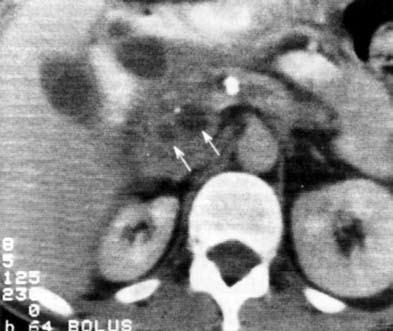

Компьютерная томография (КТ) является рентгенологическим методом высокой разрешающей способности, достаточно широко используемым при исследовании ПЖ. В принципе метод позволяет получить данные, аналогичные УЗИ, однако в ряде случаев дает возможность уточнить последние, например, при ожирении больного, наличии метеоризма, преимущественной локализации изменений в области хвоста железы (рис. 140).

Вместе с тем встречаются случаи, когда очаговые изменения, выявленные при УЗИ, не обнаруживаются при КТ (изоденсны), или наоборот и, таким образом, оба исследования дополняют друг друга. Учитывая высокую стоимость КТ, ее применение следует считать необходимым в случаях, когда на основании УЗИ не удается создать достаточно четкое представление о патологических изменениях в ПЖ (образование изоэхогенно частично).

В норме поджелудочная железа определяется на компьютерных томограммах в виде относительно гомогенного образования S‑образной формы. Признаками поражения железы являются неоднородность ее тени с участками уплотнения и разряжения, расширения, сужения и деформации протоков, одиночные или множественные полостные жидкостные образования. Для ложной кисты, как и при УЗИ, характерно наличие капсулы и однородное или неоднородное (при наличии в полости секвестров или замазкообразного детрита) содержимое. Высока разрешающая способность КТ при наличии в железе обызвествлений и протоковых конкрементов. Злокачественные новообразования выглядят при КТ очагами, плотность которых ниже плотности железы.

Рис. 140. КТ при хроническом кальцифицирующем панкреатите. На снимке видны кисты головки ПЖ, расширенный ГПП и кальцинат в его просвете.